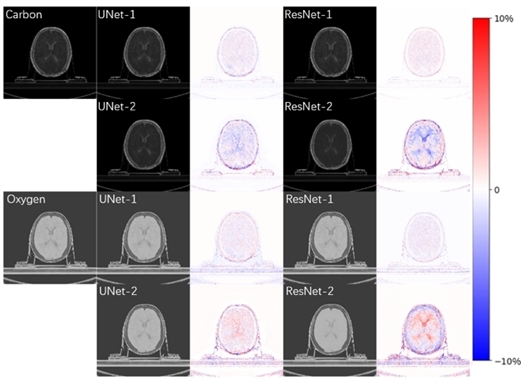

利用双能CT图像和机器学习精确提取脑部组织中碳氧质量分数模型(UNet/ResNet) 彭浩供图

在线监测的原理是利用质子束通过核反应诱导产生的正电子素(11C和15O为主要来源),并借助人工智能算法,快速准确地重建出辐射剂量分布。因此,获取人体组织的碳氧元素是非常重要的一步。传统基于单能CT的校准算法在分析人体组织(尤其是软组织)的成分时存在较大误差,限制了基于机器学习的在线剂量监测框架的应用。相比于单能CT,双能CT重建出两个不同能量下的图像,能提供更多维度的人体组织特征信息。团队利用UNet和ResNet两个模型,在软组织和低密度组织中实现了碳氧成分的准确估计(低于5%的误差)。相比与传统的单像素点方法,机器学习模型充分利用了图像的空间相关性,对图像噪声和伪影也表现出了更好的鲁棒性。这一研究成果不仅可以用于改善治疗计划,也可以用于提高机器学习所需的训练数据的准确度。